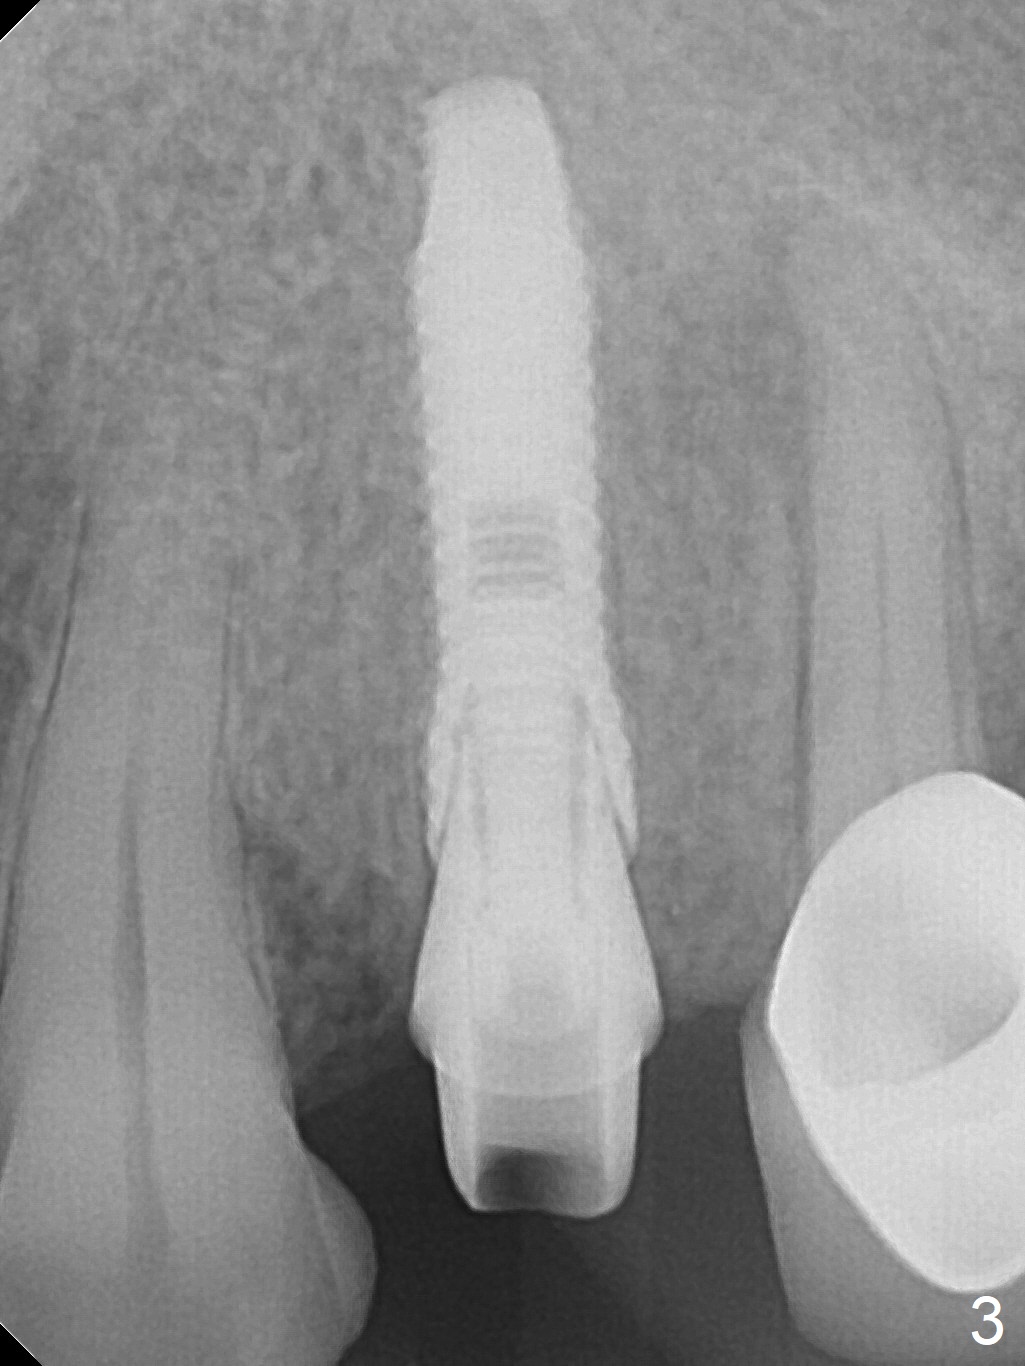

After extraction of the oval-shaped residual roots at #12 (Fig.1), osteotomy is initiated in the palatal socket for 18 mm; since the root of the canine curves distal (Fig.2 red dashed line), the osteotomy cannot afford to move mesial and extend more apical.  A 3.8x15 mm implant is placed with > 50 Ncm (Fig.3).  With immediate placement of a 4.5x4(3) mm abutment, an immediate provisional is fabricated to close the sockets (Fig.4 P).  The provisional has clearance from the RPD clasps (Fig.5).  In fact the implant could be longer, as shown by immediately postop panoramic X-ray (Fig.6).  The implant seems to be osteointegrated 3 months postop (Fig.7).  The tooth #13 is symptomatic with caries (Fig.8 C) 7 months post #12 crown cementation; the #13-15 FPD dislodges.  The upper left quadrant is cold and hot sensitive 2.5 months post RCT (Fig.9); although there is mild percussion at #13, pulpal test shows that the tooth #15 has lingering pain.  The FPD was recemented temporarily after RCT; it cannot be removed.  The implant crown has been loose for several months during the pandemic before he returns 2 years 7 months post cementation.  In fact the abutment has been not seated completely (from Fig.3 to 9).  The crown/abutment is removed from the mouth; the crown is sectioned and separated from the abutment; the latter is reseated, but incompletely (Fig.10 <).  With suspicion of the mesial crestal contact, profile drills 4.6 and 5.5 mm are used without effect.  A new (old probably being worn) and longer (easy to turn in the narrow space) abutment is finally seated completely (Fig.11 (no gap)).  After occlusal adjustment, abutment level impression is taken for a new crown.